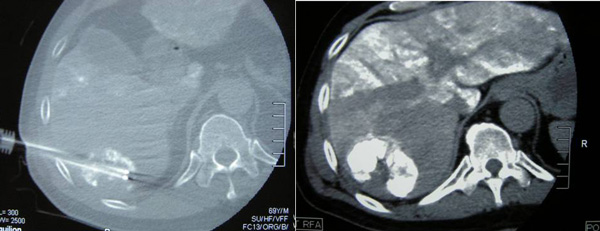

TACE was continued and on 16 September 2010, radiofrequency ablation (RFA) of the liver tumour was performed using a 2.5 x 20 cm cluster Cool-Tip RF electrode system. Two cycles of ablation were performed with repositioning of the cluster electrode in-between each cycle.

On 13 August 2011, MRI of the thoracic spine was carried out. The result confirmed a lesion measuring 3.5 x2.4 x 2.2 cm in T12 vertebra. The mass extends into the spinal canal and displacing the nerve roots. Findings are in keeping with a metastatic lesion.